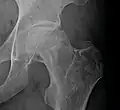

X-ray images of avascular necrosis in the early stages usually appear normal. In later stages it appears relatively more radio-opaque due to the nearby living bone becoming resorbed secondary to reactive hyperemia.[2] The necrotic bone itself does not show increased radiographic opacity, as dead bone cannot undergo bone resorption which is carried out by living osteoclasts.[2] Late radiographic signs also include a radiolucency area following the collapse of subchondral bone (crescent sign) and ringed regions of radiodensity resulting from saponification and calcification of marrow fat following medullary infarcts.

Radiography of avascular necrosis of left femoral head. Man of 45 years with AIDS. -

Nuclear magnetic resonance of avascular necrosis of left femoral head. Man of 45 years with AIDS. -